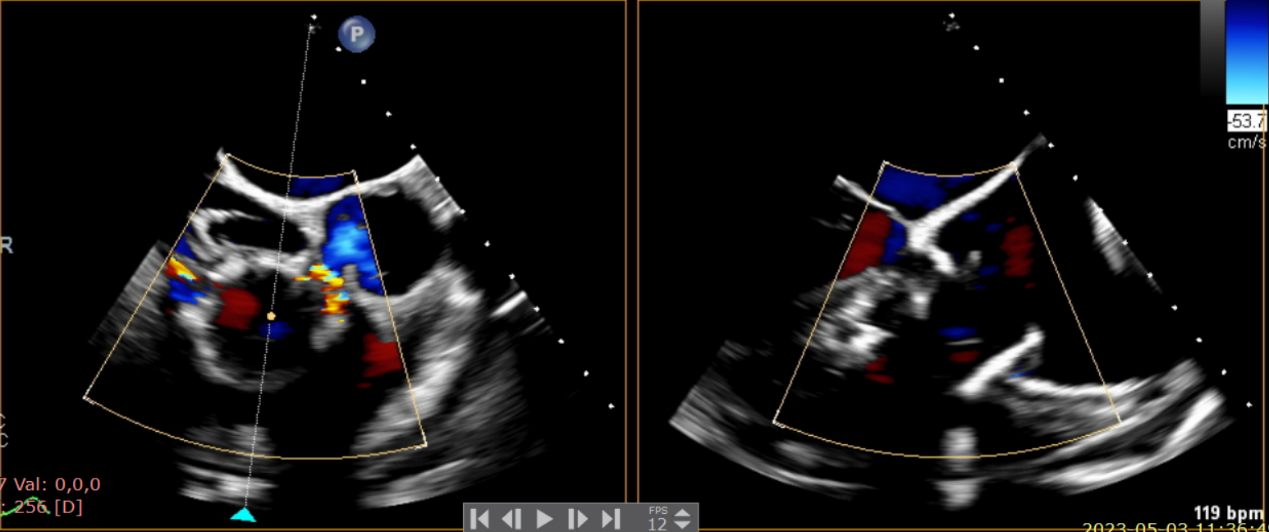

術后超聲提示無瓣周漏

術后超聲提示僅殘余輕微瓣周漏

術后Azeem Latib教授對LuX-Valve Plus經血管三尖瓣置換系統的器械性能和治療效果大為稱贊,并且認為LuX-Valve Plus的手術體驗非常好。從治療效果來看,術后即刻超聲顯示三尖瓣反流幾乎完全消失,血流動力學改善顯著,患者恢復快。在面對復雜解剖結構、超聲影像質量不佳、有起搏導線干擾時,Lux-Valve Plus也體現了極強的適應性。Thomas Modine教授參與了術中指導,他同樣再次肯定了LuX-Valve Plus術中操作的便捷性,認為LuX-Valve Plus容錯率高,對術中影像的依賴小,并表達了后期希望可以更多地應用LuX-Valve Plus三尖瓣置換系統于臨床實踐,讓更多的三尖瓣重度反流患者盡早獲益,改善預后。